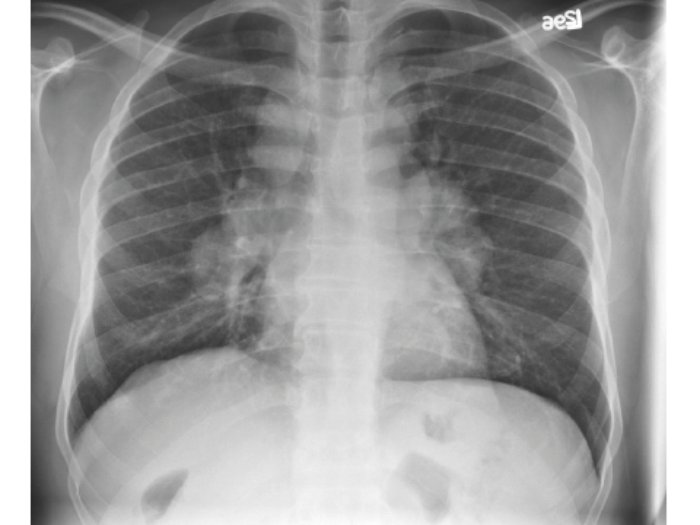

A patient with known nephrocalcinosis has a routine chest radiograph taken for shortness of breath.

- What does this chest radiograph show?

- What is the likely diagnosis?

-

Bilateral hilar lymphadenopathy.

When in association with nephrocalcinosis, sarcoidosis is the likely diagnosis.